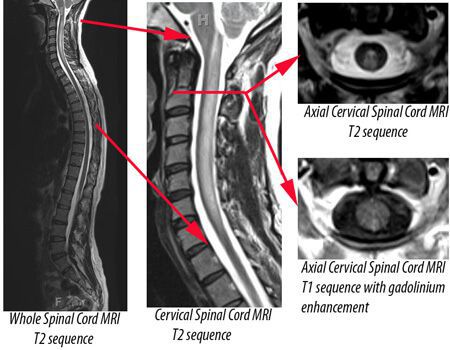

Tests that can indicate a diagnosis of transverse myelitis and rule out or evaluate underlying causes include: Magnetic resonance imaging(MRI) produces a cross-sectional view or three-dimensional image of tissues, including the brain and spinal cord.